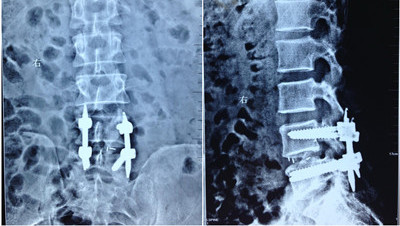

近日院长骨二科教授贺西京、王栋副主任、李锋涛主治医师及赵波主治医师,应用Mis-TLIF技术治疗了数名腰椎间盘突出症、腰椎管狭窄及腰椎滑脱患者,术中通过精确定位,应用扩张通道沿椎旁多裂肌间隙逐渐扩张,暴露手术操作区域,最大限度地保护了椎旁肌肉的破坏,另外,手术入路为经椎间孔入路,绕硬脊膜外侧进入突出的椎间盘区域进行操作,避免了术中牵拉神经而引起的术后下肢症状。术中创伤小(切口约3cm左右)、出血少(平均每个间隙出血约30ml)、术后恢复快(术后3-5天戴支具下床活动),受到了患者和家属的一致好评。